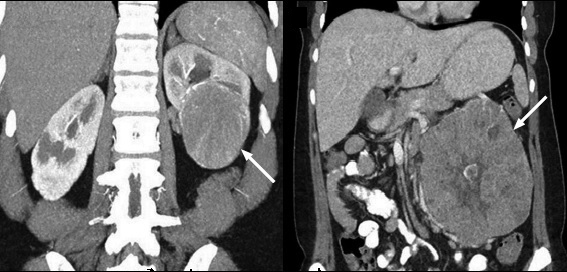

Subtipo células claras

Representa el subtipo más común (70%), se origina a partir de la corteza renal y tiene un componente expansivo. Este tumor tiene un alto contenido de lípidos con áreas de necrosis y focos hemorrágicos, por lo que su característica principal es la heterogeneidad (9); gracias a su amplia red de capilares y vasculatura, con el medio de contraste el realce es evidente en la fase corticomedular de 149 +/- 46 UH, y en la fase excretora con 95 +/- 17 UH aproximadamente 8.

Una vez detectado el tumor se debe proceder a ubicar la extensión del mismo, correlacionándose en un 45% con extensión a la vena renal y metástasis a pulmón, hígado y hueso (2). La tasa de supervivencia a 5 años es del 50% 10 (Fig. 10, Fig. 11).